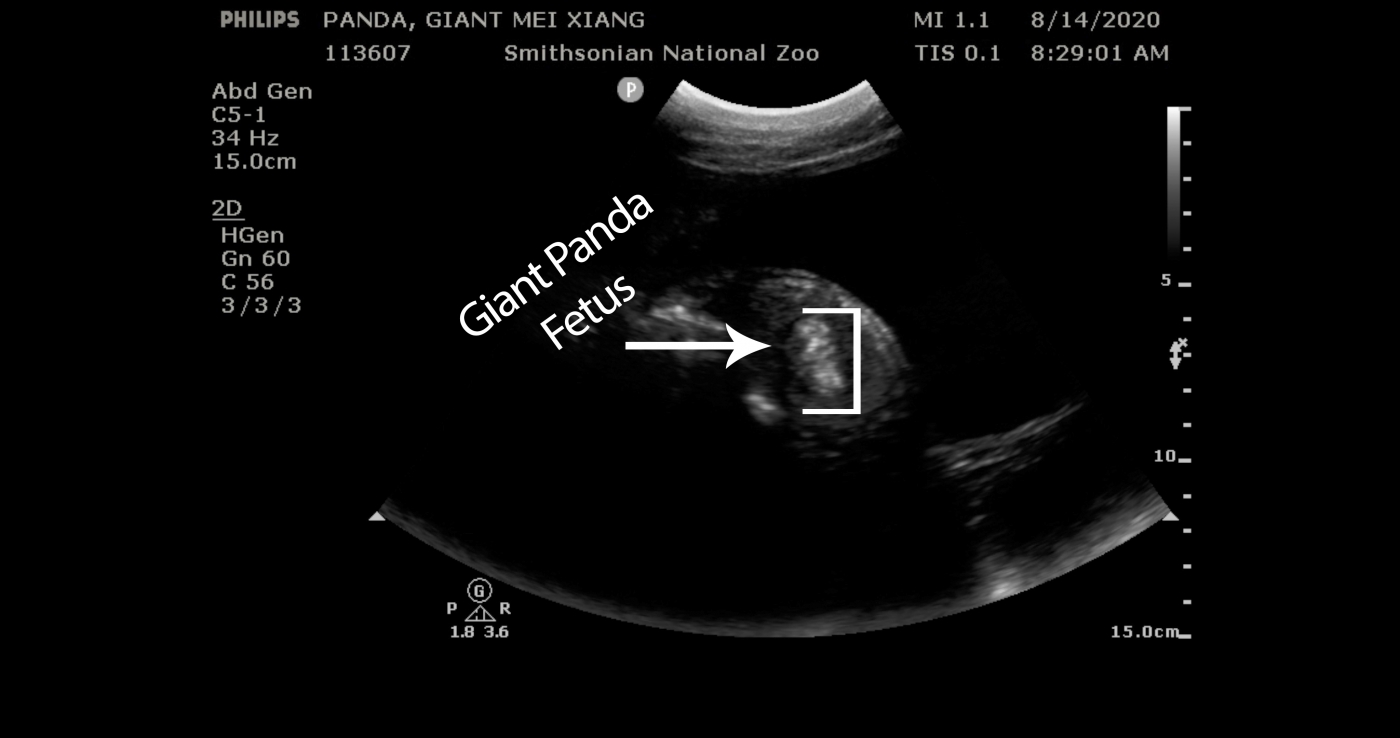

Neiffe周一对美香进行了超声波检查,结果显示它的胎儿在羊水中“踢动和游泳”,以及清晰可见的脊柱和血流。